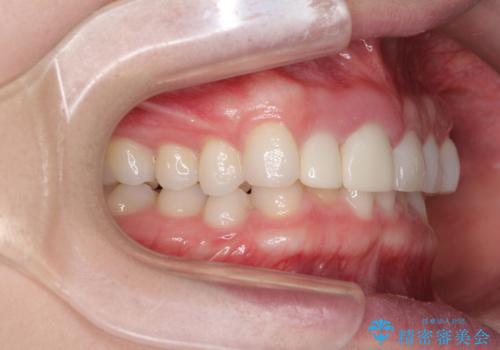

その後、他院で気になる前歯をセラミッククラウンで補綴治療をしたそうですが、やはり歯列を整えたいとのことで再度来院されました。

クラウンの状態は、根管治療の状態も含めて決して良い状態とは言えず、矯正治療後の根管治療と補綴治療の再治療を前提として、インビザラインによる矯正治療を行うこととしました。

矯正治療中に前歯2本のクラウンは外れてしまい、途中仮歯に替える必要があったので期間は掛かりましたが、歯列も整い、負担のかからない咬み合わせを達成することができました。